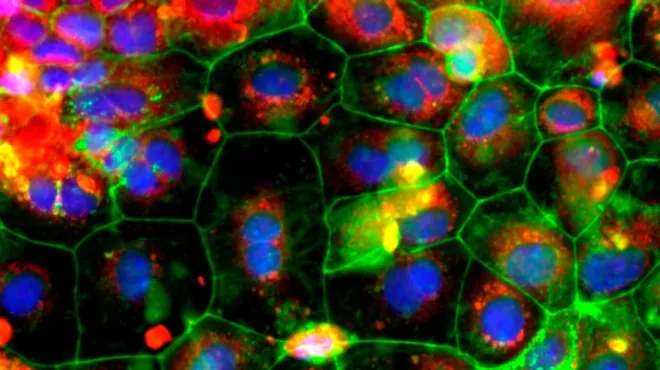

Celle- og genterapier bygger på grundig forskning, der bygger på mange årtiers videnskabelige fremskridt. De centrale redskaber og teknologier er blevet afprøvet og raffineret af utallige eksperter – først i laboratoriet og sidenhen i klinikken. Ved celleterapi dyrkes eller modificeres cellerne uden for kroppen, før de indsprøjtes i patienten, hvor de udvikler sig til et "levende lægemiddel". Ved genterapi udskiftes, inaktiveres eller indføres generne i celler – enten uden for eller inde i kroppen – for at behandle en sygdom. Nogle behandlinger kvalificerer sig som både celle- og genterapier.

Den enkelte celle- og genterapi udvikles på grundlag af detaljeret information om årsagerne til en patients sygdom. Den behandler en tilstand eller sygdom ved kilden ved på genniveau at reparere eller forbedre celler. Hos Novartis samarbejder vi inden for celle- og genterapi for at bringe denne revolutionerende behandlingsform til patienter med en lang række sygdomme, herunder genetiske sygdomme og visse livstruende kræftformer.

Alle disse behandlinger lever op til betegnelsen præcisionsmedicin – en term der vandt udbredelse, første gang videnskaben fastslog DNA-sekvensen i hele det menneskelige genom. Den gang drømte forskere om at udnytte information om hvert enkelt menneskes gener til at skræddersy behandlinger til patienter og dermed fundamentalt forandre lægevidenskaben. Celle- og genteknologi bringer os tættere på dette ambitiøse mål.